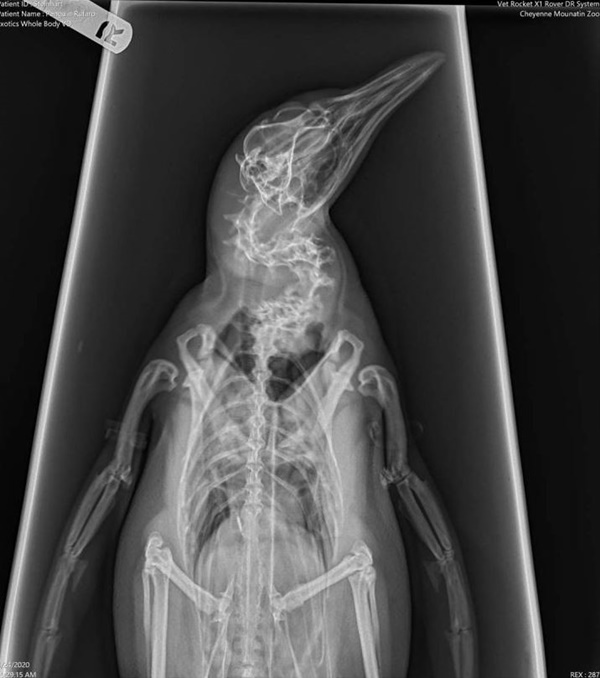

공개된 사진 속에는 펭귄 한 마리의 엑스레이 분투기가 담겨있다.

설명에 따르면 건강검진을 맞이해 펭귄의 엑스레이를 찍어야 했다고 한다.

펭귄은 원통에 갇혀 가만히 있었고, 그 사이 수의사는 재빠르게 엑스레이 촬영을 마쳤다.